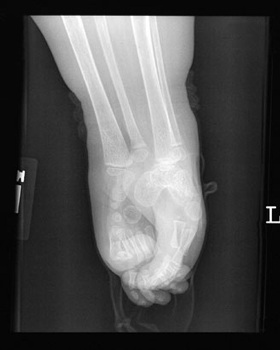

Hình ảnh chụp X quang cho thấy chân của Shiloh bị dính vào nhau. Ảnh chụp năm cô bé 4 tuổi. |